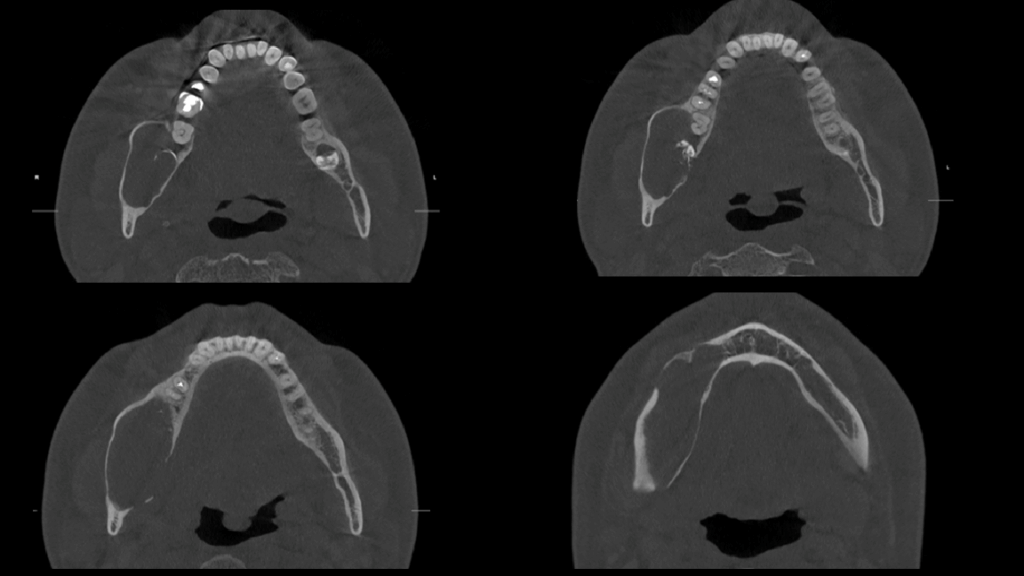

A la evaluación de la tomografía volumétrica (cone beam) bimaxilar en los cortes axiales (Figura 2), coronales, (Figura 3) y tangenciales (Figura 4) se observa imagen isodensa irregular, ubicado en cuerpo, ángulo y rama ascendente mandibular de lado derecho, que se extiende desde zona periapical mesial de pieza 44, hasta tercio medio de rama mandibular, y desde tercio superior (próximo a base de apófisis coronoides) hasta basal mandibular ocasionando expansión de tablas ósea, adelgazamiento de corticales y pérdida de continuidad de tabla vestibular en zona de pieza 45 y de tabla ósea lingual a en zona de pieza 46, 48 y rama mandibular. Además de producir el desplazamiento caudal y borramiento parcial de las corticales del canal mandibular; así mismo, se observó reacción periostal en tabla ósea vestibular (próxima a escotadura sigmoidea), ángulo mandibular y en basal mandibular de zona antegonial. Se pudo evidenciar tambien a la pieza 48 incluida y con reabsorción severa 48 dejando solo restos de esmalte.

CORTES AXIALES

CORTES CORONALES

CORTES TANGENCIALES